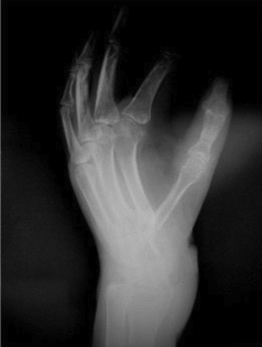

Postoperative recovery was uneventful, and early hand physiotherapy commenced 2 weeks after wound healing was achieved. In the 1-year follow-up, the thumb and thenar eminence had healed well with no concerns regarding wound healing nor scar appearance (Figure 10). Sensation was restored with light touch and 2-point discrimination being present. Active movements, such as MCPJ extension and a hook grip, were restored (Figure 11). A radiograph showed the first carpometacarpal joint in a good position with the fracture having healed without any bone resorption (Figure 12). The iliac crest bone graft used to reconstruct the second metatarsal had also healed well (Figure 13).